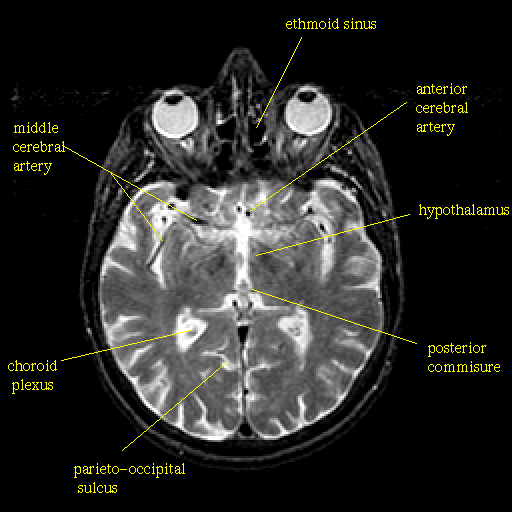

T2-weighted structural MR: Slice 25

Slice 25